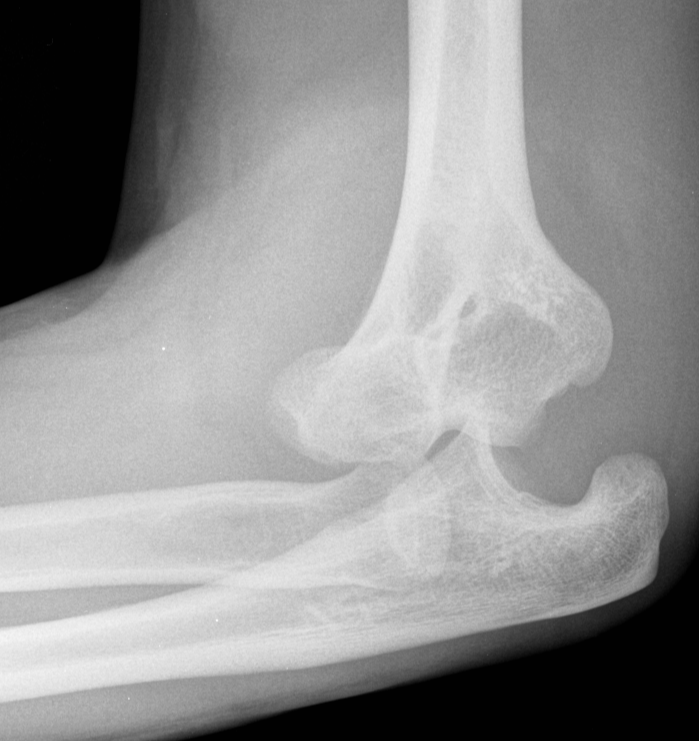

3. Elbow dislocation